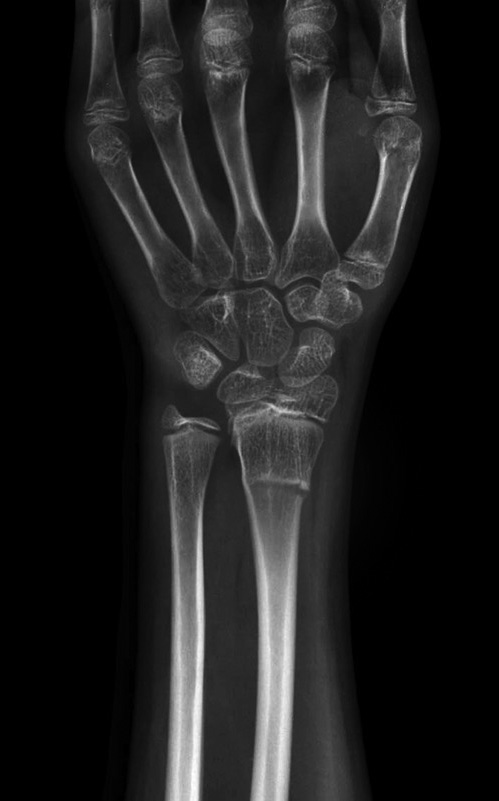

Is there a test for distal radius fractures?

Yes! Often fractures are obvious on physical examination, but severe sprains and contusions can also look and feel very much like a wrist fracture. X-rays or CT scans usually offer definitive diagnoses for wrist fractures.